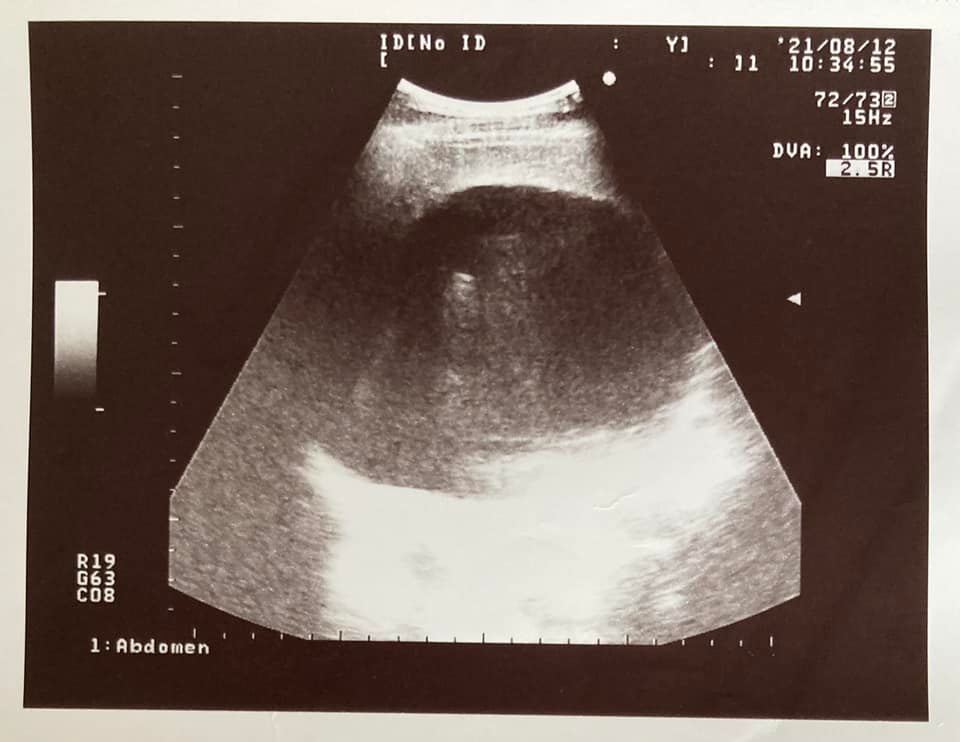

知名作家苦苓(王裕仁)曝光一年前的日記,揭露「我帶著肝臟中的14.5公分腫瘤,和超過400萬個B肝病毒,努力的活下去」,原以為上山下海、出國遊玩或跑通告,都未覺得力不從心的他,其實罹癌前就有出現徵兆,包含身體莫名痠痛、耳鳴與嘴裡出現鹹味,即使看了多名醫師都未改善,事後才察覺這些都是前兆

苦苓今(1日)於臉書曝光2020年元旦的日記,內文一開頭就直言「新年的第一天,我帶著肝臟中的14.5公分腫瘤,和超過400萬個B肝病毒,努力的活下去。」他自嘲是自大狂,以為體力相當好的他,未出現多數上年紀人會憂心的三高與心血管疾病,加上母親已86歲,讓他自認為可以長命百歲。